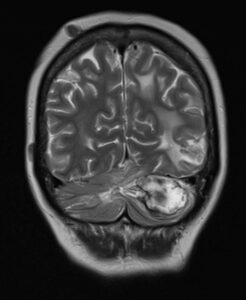

RM CORONAL T2